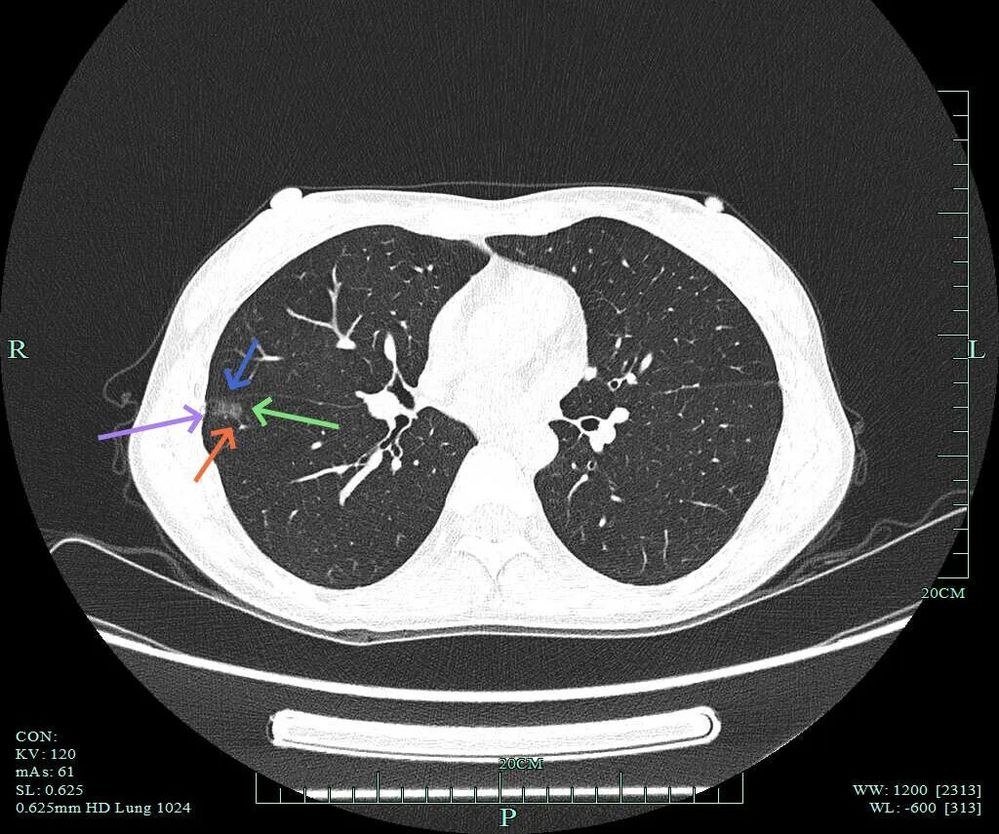

薄层上病灶出现,靠叶间裂处密度高呈实性成分,边上是磨玻璃成分,轮廓较清。

病灶处叶间裂密度较高,灶内有条状偏高密度,磨玻璃成分较淡。